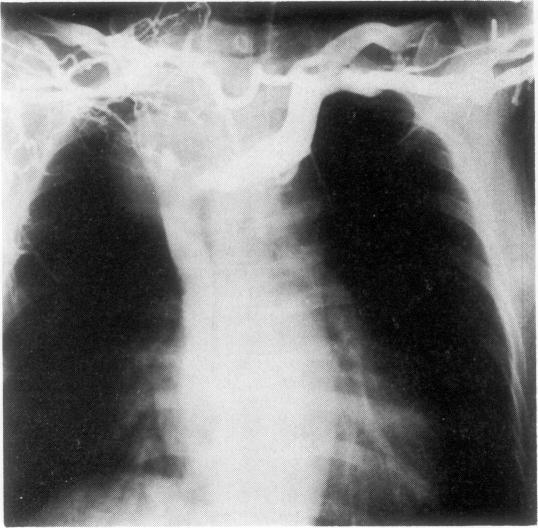

浸润气管的甲状腺癌切除术。

Resection of thyroid carcinoma infiltrating the trachea.

We have treated surgically 11 patients with thyroid carcinoma that had infiltrated into the trachea. Three patients had primary tumours, and eight had recurrent tumours after previous operations. Sleeve resection of trachea was performed where thyroid carcinoma had proliferated; the trachea was reconstructed by end-to-end anastomosis. In two patients 10 rings of the trachea were resected. In three patients the anterior half of the cricoid cartilage was resected along with the cervical trachea. In one patient tracheoplasty was performed using partial extracorporeal circulation because severe tracheal stenosis prevented endotracheal intubation. Two of the 11 patients died from the surgery and one from disseminated metastases. One patient who had undergone tracheal resection for thyroid carcinoma three years and five months previously had a recurrence of the tumour in the trachea adjacent to the anastomosis, and a second tracheal resection was performed. In three patients postoperative laryngeal stenosis occurred. Five patients are alive and well two years and one month to four years and seven months after their operations. The histological pattern of the tumour was papillary adenocarcinoma in all 11 patients.

我们对11例浸润至气管的甲状腺癌患者进行了手术治疗。3例为原发性肿瘤,8例为既往手术后复发的肿瘤。在甲状腺癌增生部位进行气管袖状切除术;通过端端吻合重建气管。2例患者切除了10个气管环。3例患者切除了环状软骨前半部分及颈段气管。1例患者因严重气管狭窄无法进行气管插管,采用部分体外循环进行气管成形术。11例患者中有2例死于手术,1例死于广泛转移。1例3年5个月前因甲状腺癌行气管切除的患者,在吻合口附近的气管复发肿瘤,再次进行了气管切除。3例患者术后发生喉狭窄。5例患者术后2年1个月至4年7个月健在。11例患者肿瘤的组织学类型均为乳头状腺癌。